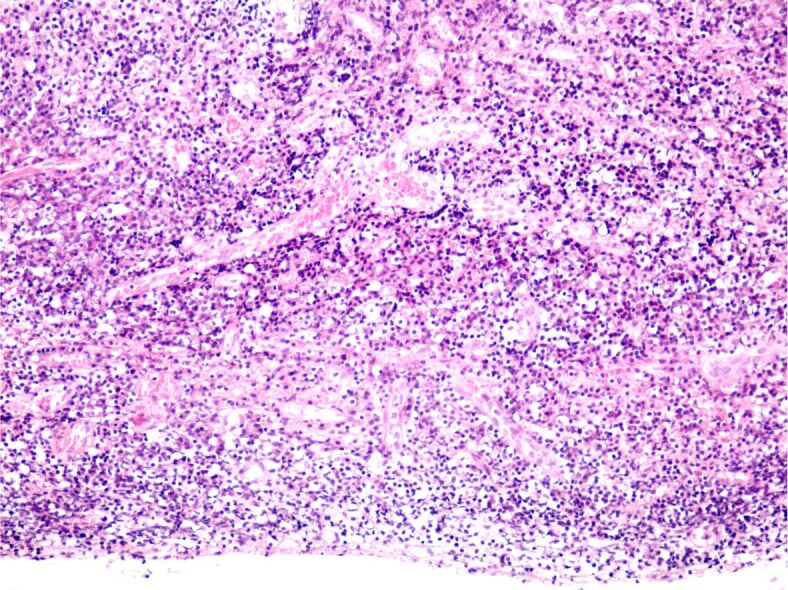

胆脂瘤是一种耳科病变,可发生于任何年龄,并可导致各种并发症,包括面瘫、颅内脓肿、听力损失、静脉血栓形成等。胆脂瘤即使被认为是一种良性疾病,但由于其侵袭性,复发的风险也很高。我们描述了一例复发性胆脂瘤病例,患者为一名年轻男孩,在 16 岁至 19 岁(2019 年至 2022 年)期间,曾因慢性耳流脓和听力下降接受过三次手术治疗。小儿胆脂瘤更容易复发。考虑到手术切除是目前唯一的治疗方法,了解胆脂瘤病变扩展的生物学特性对于进一步改善治疗管理非常重要。对与手术方法相关的血管生成、慢性炎症和免疫浸润进行深入研究可能是预防胆脂瘤复发的未来方向。

Cholesteatoma is an otologic pathology that can occur at any age and can lead to a variety of complications including facial palsy, intracranial abscess, hearing loss, venous thrombosis. Cholesteatoma, even if considered a benign condition, associates high risks of recurrency due to its invasiveness. We describe a case of recurrent cholesteatoma in a young boy who presented chronic ear discharge and hearing loss for which had undergone three surgical interventions between the ages of 16 and 19 years old, from 2019 to 2022. Pediatric cholesteatoma is more prone to recurrency. Considering surgical excision as the only treatment at the current moment, it is highly important to understand the biology of cholesteatoma lesional extension for further treatment management improvement. Good research of angiogenesis, chronic inflammation and immune infiltration correlated with surgical approach may be the future for preventing cholesteatoma recurrency.